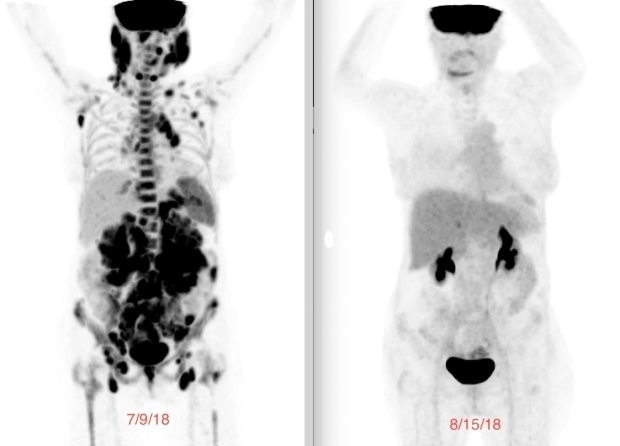

A week before the infusion, my baseline PET scan showed tumors lighting up throughout my body. Just 29 days later, the follow-up scan showed no evidence of disease. I was finally in complete remission. No one could believe it. It was astonishing how quickly and effectively it worked.

PET scan image showing a scan before and after CAR T-cell therapy. On the left, a scan with many tumors present, and on the right, no evidence of disease.

Laurie's PET scan before CART T-cell therapy (left) and after (right).